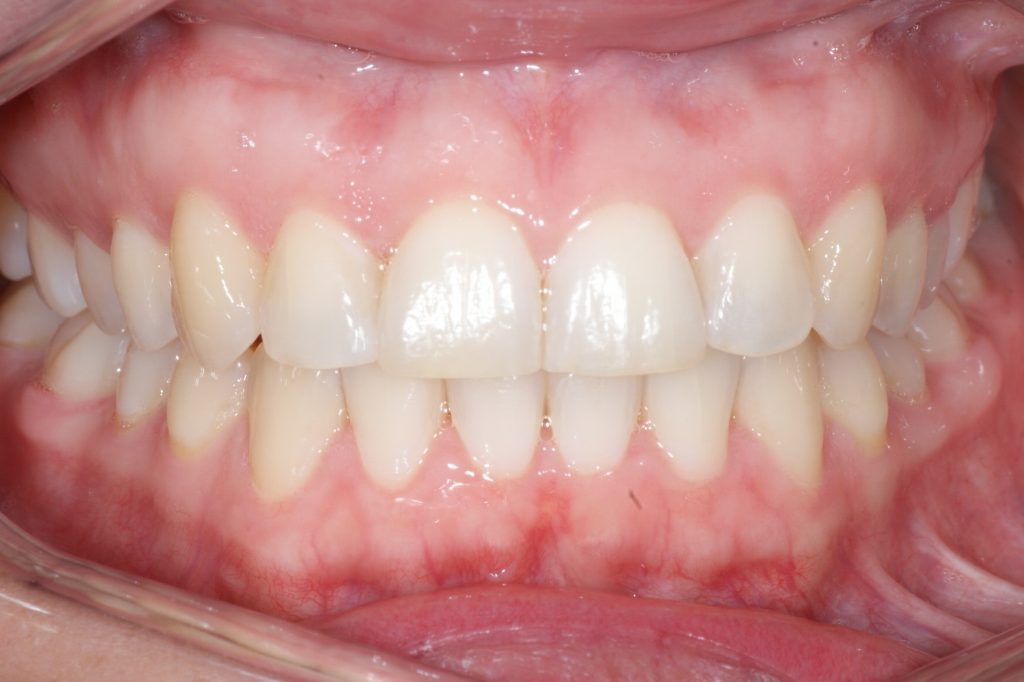

Correction d’une malocclusion de type Classe I, surplombs inadéquats et chevauchement modéré aux 2 arcades.  57 coquilles furent nécessaires pour améliorer ce sourire.  Traitement chez une adulte, réalisé en 15 mois.